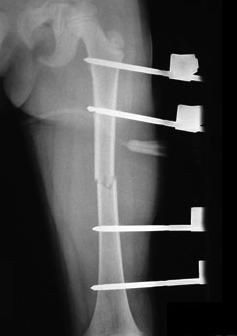

- submuscular bridge plate fixation

- indications

- unstable fractures in children 5 or older and >49kg (100lbs)

- very proximal or very distal fractures

- severe comminution

- approach

- laterally based incision and plating with minimal disruption of soft tissue envelope

- small proximal and distal incisions and plate is placed between periosteum and vastus lateralis on the lateral side of the femur

- fracture is provisionally reduced with closed or percutaneous techniques

- instrumentation

- typically use 12-16 hole 4.5mm narrow LC-DC plate with 3 screws proximal and 3 screws distal to the fracture. the plate may need to be bent to accommodate the natural bend of the femur

- Contoured femur plates are also an option

- complications

- hardware removal

- refracture following hardware removal

- outcomes

- favorable time to union, weight bearing, hardware irritation, and limp outcomes